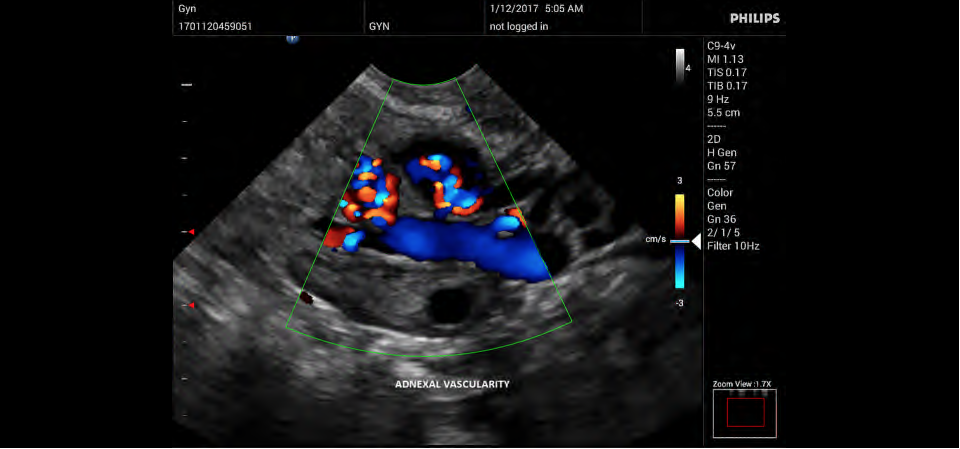

Philips InnoSight

Philips InnoSight увеличивает возможности сканирования во множестве мест оказания медицинских услуг. Благодаря данному УЗИ аппарату врачи могут не сомневаться в быстром выполнении обычных ультразвуковых сканирований во врачебном кабинете, клинике или больнице.

InnoSight позволяет перенести ультразвуковую диагностику непосредственно туда, где пациенту оказывается медицинская помощь, что повышает мобильность врачей. Этот компактный и легкий ультразвуковой аппарат позволяет чаще использовать возможности ультразвуковой диагностики и предоставляет широкий набор технологий для проведения углубленных исследований — программные пакеты для специализированного анализа, функции аннотирования и наборы готовых настроек для различных типов тканей.

Эргономичная система с высококачественными широкополосными датчиками Philips помогает повысить клиническую надежность результатов исследования и уровень оказания медицинских услуг. Аппарат можно перемещать вручную или с помощью тележки.

• Акушерство и гинекология;

• Цветное допплеровское картирование

• Направленный энергетический допплеровский режим: Дополнительно к возможностям визуализации сосудов в стандартном энергетическом режиме добавляется информация о направлении. Этот режим полезен для визуализации мелких сосудов в качестве замены цветного допплеровского картирования.

• Специализация (УЗИ) - Общие исследования, Гинекология и акушерство

• Конвексный УЗИ датчик Philips C9-4v